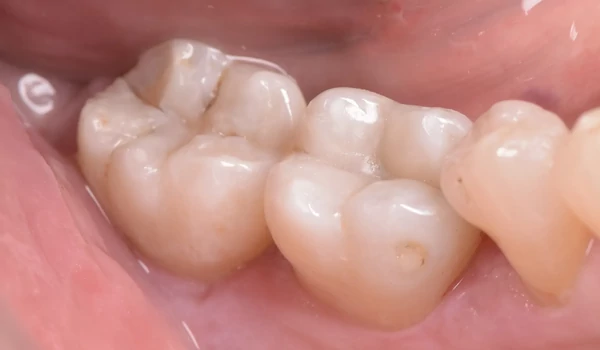

ESETBEMUTATÁS Kiinduló helyzet 1. ábra: kiindulási állapot – régi amalgámtömések a 46-os és 47-es fogban A páciens a jobb alsó első és második moláris (46 és 47, FDI jelölés) amalgámtöméseinek cseréjére jelentkezett. A választott megoldás a CLEARFIL MAJESTY™ ES Flow Universal LOW alkalmazása volt egyetlen restaurációs anyagként. A fogak pozíciója lehetővé tette az egyszerű színválasztást: az U (universal) árnyalat tökéletesen megfelel minden hátsó restaurációhoz.

1. ábra Két kicserélendő amalgámtömés. |